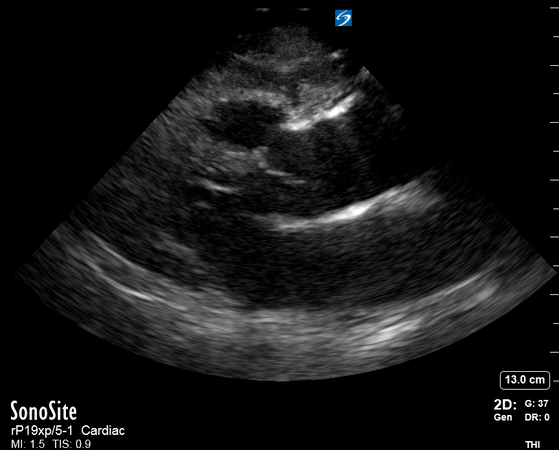

The PLAX view is versatile and allows the recognition of multiple landmarks, making it good for visual estimation of LV contractility. It is essential to optimize the view ensuring a true sagittal long axis, as being oblique to the LV chamber may underestimate its size and overestimate its emptying. The PSAX view at the level of the papillary muscles reveals the entire muscular circumference and concentric squeeze of the LV. It is useful to estimate both global function and focal wall motion abnormalities. The A4C view, although technically challenging, provides good insight into the global myocardial function and chamber size.

LV CONTRACTILITY

Qualitative assessment of the LV and visual estimation of Ejection Fraction is based on three parameters:

Endocardial excursion.

Myocardial thickening.

Movement of the anterior leaflet of the mitral valve.

A qualitative assessment is typically categorised as:

Normal (LVEF 50-65%)

Moderately Depressed (LVEF 30-50%)

Severely Depressed (LVEF < 30%)

Hyperdynamic (LVEF > 65%)

SIGNIFICANTLY IMPAIRED / DILATED LV

A severely depressed LV contractility, particularly when paired with a plethoric IVC or lung B-lines, indicates systolic heart failure. Chronically raised afterload can lead to severe dilation of the LV.